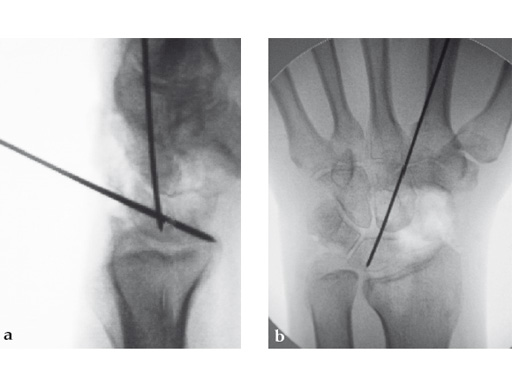

Fig 2ab Dorsal intercalated segment instability correction and K-wire fixation.

Fig 3ab Bone debridement. Guide positioning and fixation.

Fig 3c Bone debridement. Guide positioning and fixation.